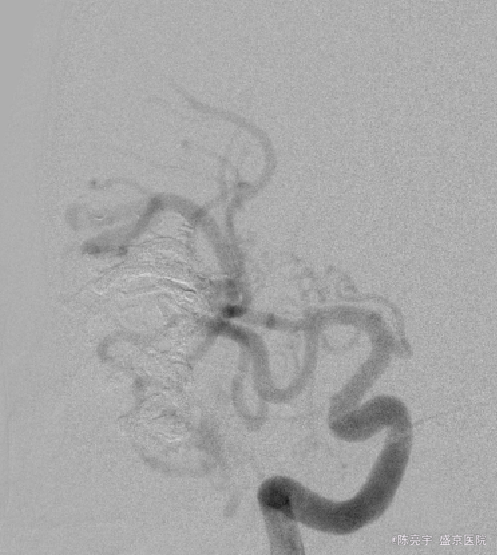

诊断:颅内血管畸形 治疗:全麻下血管畸形介入栓塞术

术后好